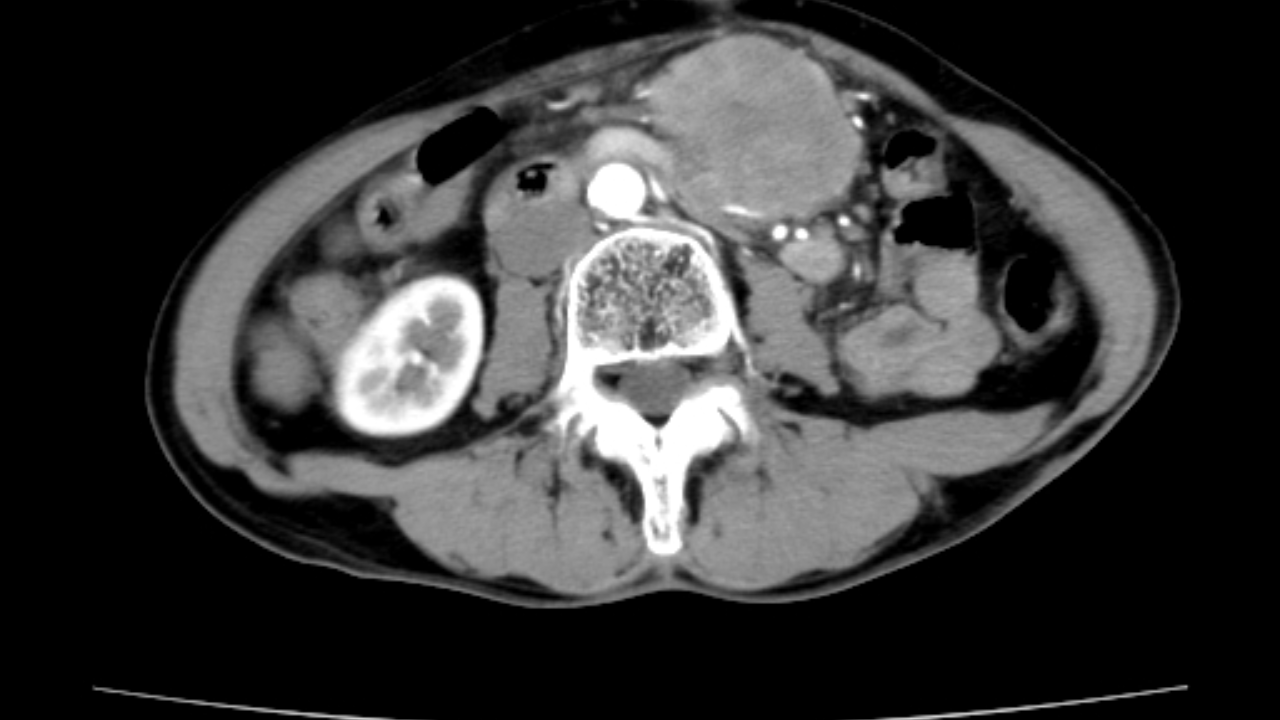

辅助检查:腹部B超提示上腹部不规则低回声包块,腹部CT检查提示腹腔多发占位性病变,考虑良性可能(如下图所示)。

动脉期

门脉期

延迟期

临床诊断:腹腔多发占位性病变性质待查。